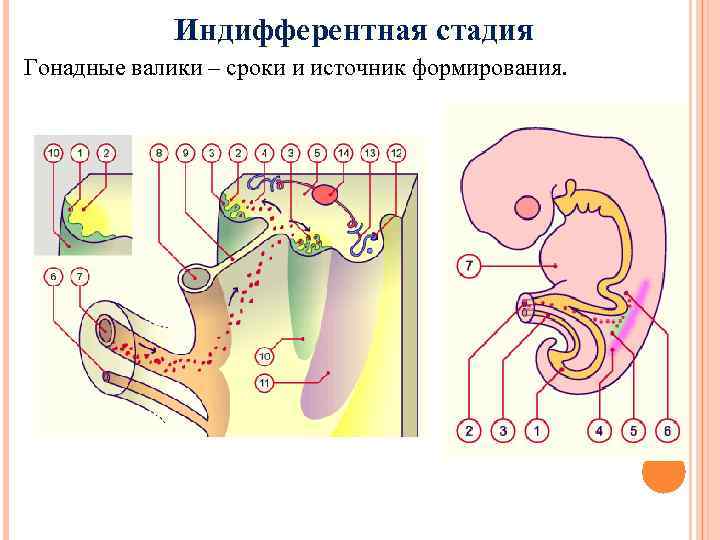

Индифферентная стадия Гонадные валики – сроки и источник формирования.

Индифферентная стадия Гонадные валики – сроки и источник формирования.